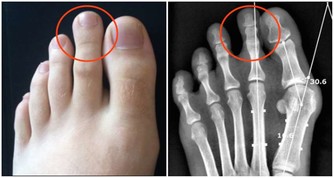

結腸癌其他的常見病症包括,體重驟減、食慾不振、噁心乾嘔、直腸出血或便血、頻繁腹瀉或便秘、大便沒有淨感、腹脹腹痛等。當上述症狀連續出現兩週左右時,建議立即前往醫院診治,盡量不要拖延。